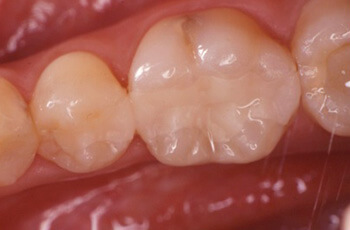

症例1:大、小臼歯の虫歯をセラミックインレーで修復しました。